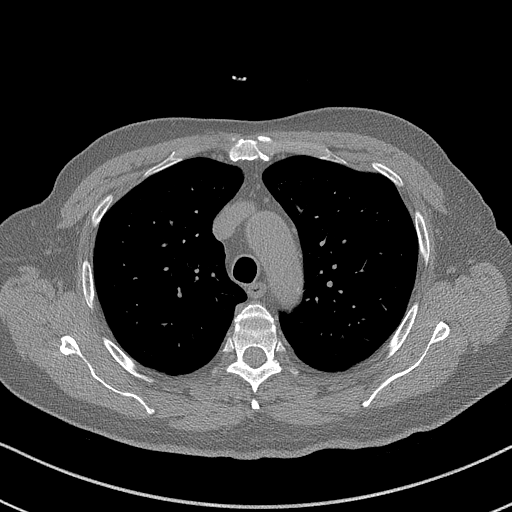

GT

FBP

HQS-CG

DuDoNet

Meta

Meta_re

EPNet

Qualitative Results Comparison. We also visualize the reconstruction results of these methods on AAPM-test and COVID-test datasets. As in the first three rows of Fig. 4, the reconstructed images from ours and retrained MetaInvNet show the best visualization quality on AAPM-test set across different angle numbers. Besides, our results show sharper details with the additional utilization of in the projection domain. When testing the reconstructed image on the COVID-test set, our result also gives sharper details but with more artifacts since the data distribution is very different. Although HQS-CG has achieved better quantitative results on the COVID-test dataset, the reconstructed image of their model in the fourth row is even smoother than FBP.